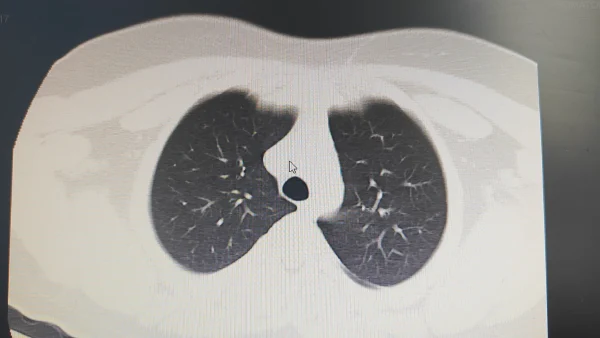

肺水肿,这个听起来让人揪心的医学名词,或许并不像你想象得那么遥远。不久前,64岁的王先生因呼吸困难就医,被诊断为双肺间质性肺水肿。我们在这里不仅要介绍肺水肿的详细内容,还要与大家分享如何预防和治疗这种疾病。

肺水肿实际上是由于各种原因导致的肺部积液,主要表现为呼吸困难、咳嗽、和胸部不适。这种病症非常普遍,但如果不及时治疗,可能会严重影响生活质量,甚至危及生命。

肺水肿的成因复杂,不仅仅限于心脏病。根据医学研究,心功能不全仍然是最常见的原因,这涉及到心脏无法有效地将血液从肺部泵出,导致血液反流进肺,液体渗入肺泡。同时,感染性病原体、毒物暴露或肾功能不全也可能引发间质性肺水肿。

一项发表于《新英格兰医学杂志(NEJM)》的研究指出,心源性肺水肿是最常见的类型,占所有病例的60%至80%(Smith et al., 2022)。此外,非心源性肺水肿,包括急性呼吸窘迫综合征(ARDS),也在老年人群中具有较高发生率(Brown et al., 2021)。我们必须了解这两者的区别和相互关系。